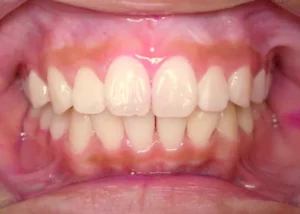

正面

- After